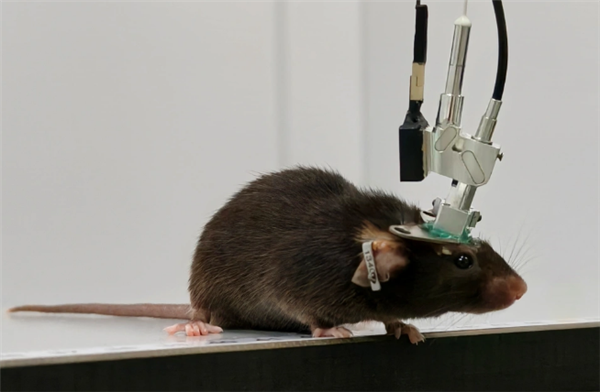

迈向混合智能系统的关键一步——“人脑芯片”一周学会复杂电脑游戏

在生物计算领域,一项新成果将科幻般的构想向现实推进了一步:澳大利亚生物技术公司CorticalLabs研究人员演示了一种由人类脑细胞驱动的计算机芯片平台CL1,在一周内学会了运行经典的第一人称射击游戏。而让生物系2026-03-05 -